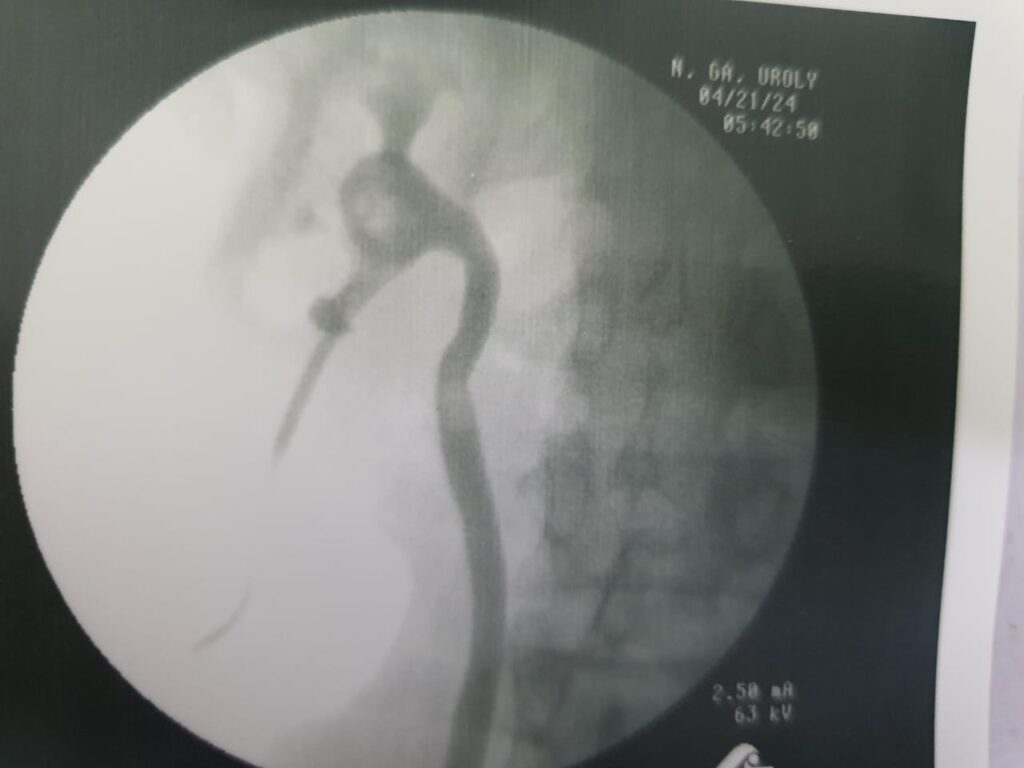

Case of 45-year-old male.

History : Patient presented with recurrent flank pain, urinary frequency, and occasional blood in urine.

Lab Findings: Elevated serum creatinine and mild electrolyte imbalance.

Imaging: Ultrasound and CT KUB revealed multiple kidney stones causing partial obstruction.

Diagnosis: Obstructive uropathy due to multiple renal calculi.

Treatment Provided::

- Minimally invasive stone removal procedure

- Medical therapy for pain and infection prevention

- Dietary and hydration counseling for stone prevention

- Regular monitoring of kidney function

Outcome : Patient achieved complete stone clearance with improved renal function and relief from symptoms.

Next Step: Three-month follow-up with ultrasound and renal function tests to ensure no recurrence.